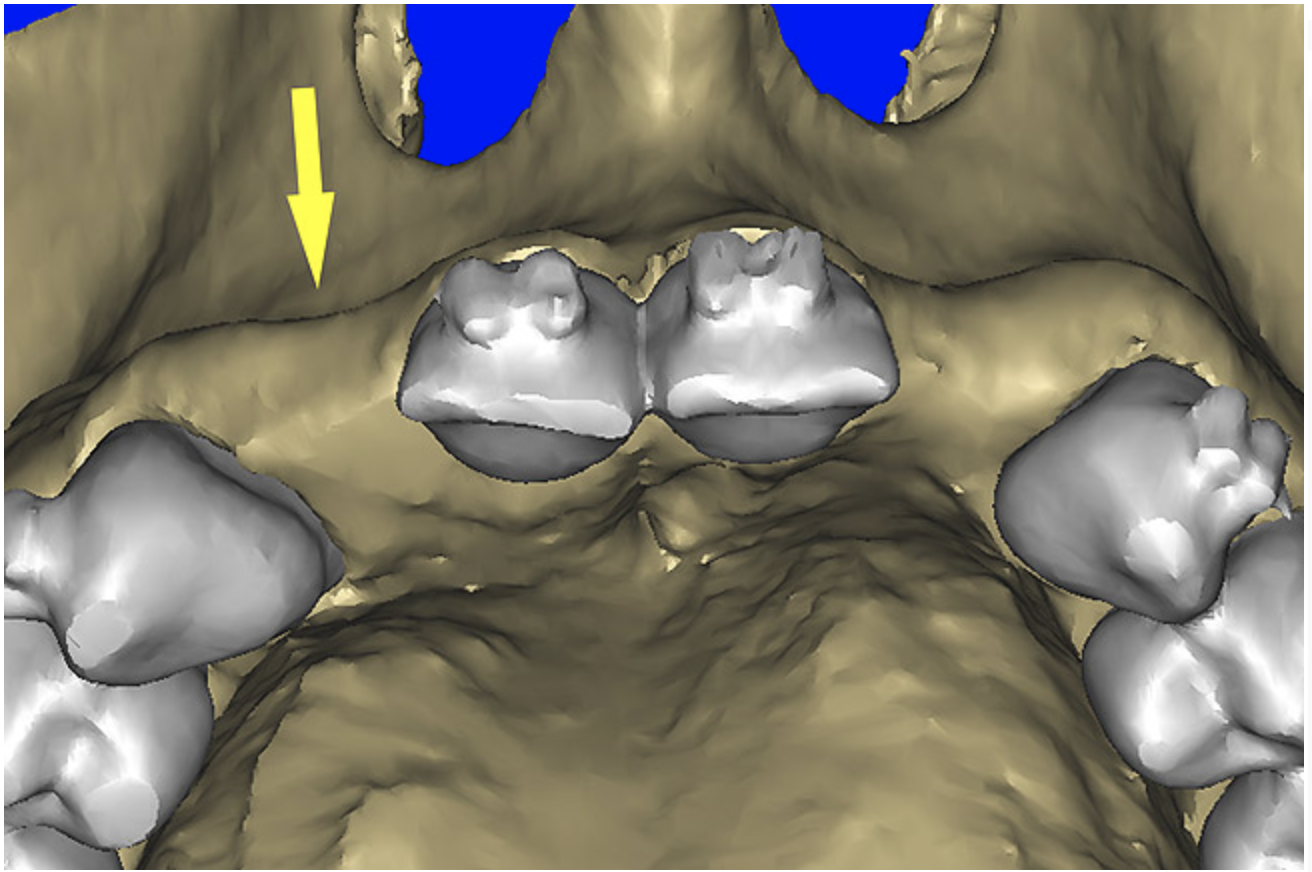

The CT axial views represent an important instrument in gaining a better understanding of anatomical features that can not be determined by any other imaging modality (Figure 6A). When the maxilla is sliced axially at the level where the roots meet the crest of the bone, the adjacent and surrounding root morphology can be revealed. Of note are the individual and different shapes of each of the central incisors, canines, premolars, and molar roots. These images reflect a phenomenon defined by the author as the “restorative dilemma.” Clinicians encounter this often difficult dilemma when attempting to re-establish morphologically correct emergence profiles in prosthetic teeth as they ascend from the round shape of the implant(s). When planning for the placement of the implant in the left lateral incisor area, there appeared to be adequate mesial-distal space between roots as seen in the axial view of Figure 6B. A closer inspection of the planned site for the right lateral incisor revealed a more narrow space, further.complicated by the distal rotation of the palatal aspect of the tooth root. Based on this preliminary position, the 3.75-mm diameter, straight-walled implant can be seen encroaching on the lamina dura periodontal ligament space of the right canine and central incisor. If there was not adequate room for this diameter and type of implant, the adjacent teeth could sustain potential iatrogenic damage. Therefore, additional “tweaking” of the virtual placement was necessary to diminish this risk.

Figure 6a  By slicing the maxilla axially, the images revealed (A) the differing morphology of the central incisors, canines, premolar, and molar roots, and (B) the left simulated implant seen encroaching on the adjacent lamina dura.

Figure 6a

Figure 6b  By slicing the maxilla axially, the images revealed (A) the differing morphology of the central incisors, canines, premolar, and molar roots, and (B) the left simulated implant seen encroaching on the adjacent lamina dura.

Figure 6b